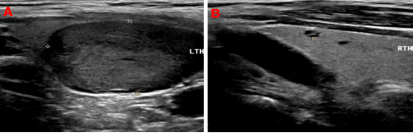

99mTc-MIBI甲状旁腺SPECT/CT融合显像图:图1+2冠状位、图3+4矢状位、图5+6横断位,提示功能亢进甲状旁腺组织(十字线交叉处)。随后的超声提示:双侧甲状旁腺区多断面超声扫查未见明显异常占位性病变;双侧甲状腺结节,其中左侧叶内一枚33mm×19mm低回声、边缘光滑、内无强回声结节。颈部B超图:A、B(纵切面)分别显示甲状腺左叶、甲状腺右叶;左叶内一低回声结节。

临床资料和核医学检查高度怀疑患者存在原发性甲状旁腺腺瘤,但超声检查尚不支持。为此,老年科吕荣主任医师团队、核医学科尤徐阳主任医师团队、介入科徐斌主任医师团队进行了多学科MDT讨论,认为:患者甲状旁腺功能亢进症诊断明确,高度可疑甲状旁腺腺瘤病灶可能起源于少见的甲状腺内异位甲状旁腺组织,或者是因为甲状旁腺腺瘤组织向上生长推移到甲状腺内;该病灶包膜完整,边界清晰,颈部未见明显肿大淋巴结,排除为恶性病变;患者年老体弱,合并多种疾病,可采取超声引导下可疑病灶组织穿刺证实,可疑病灶一旦确定为甲状旁腺来源,可立即行超声引导下病灶消融术。患者及家属对当前及下一步诊疗方案满意,希望能够通过微创治疗方案解除痛苦。